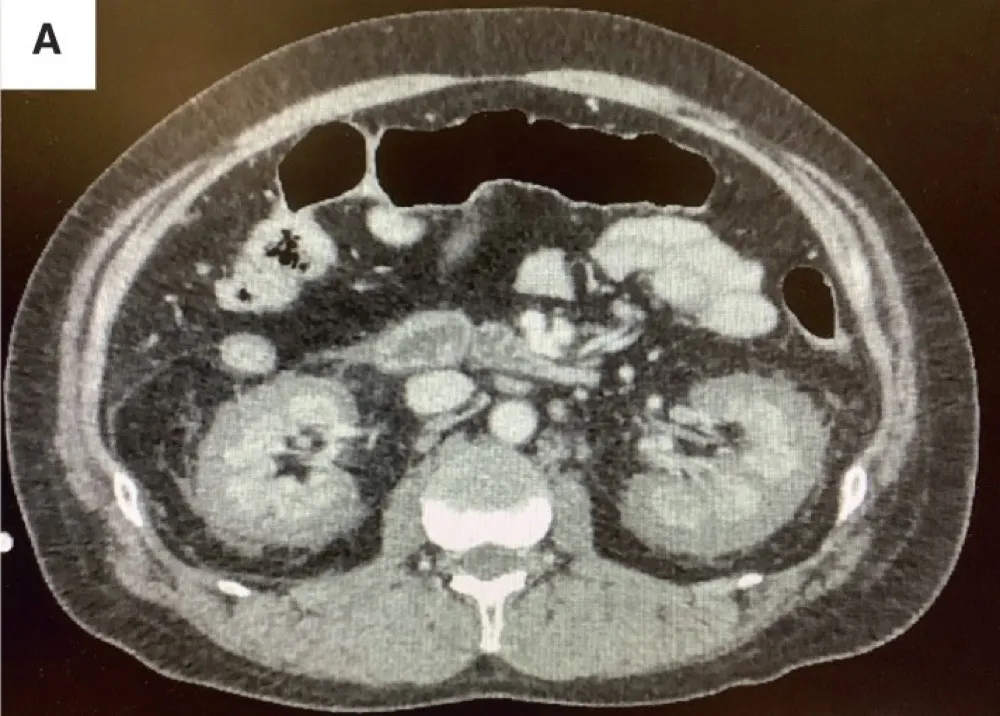

Uma causa incomum de hematúria glomerular intermitente!

Hematúria pós infecção, caso clínicos para auxiliar no entendimento de causas glomerulares comuns e raras...